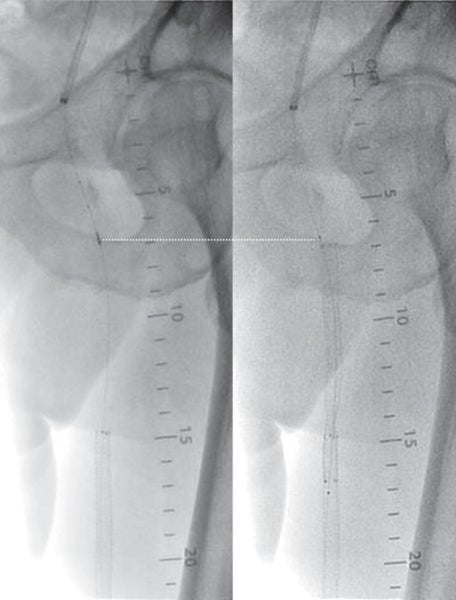

対側CFAより6 Fr 45 cm長のガイディングシースを挿入し山越えにて左EIA遠位部に進めた。この時点で圧波形は問題なかったため、手技を継続することとした。まず、5.5 Fr 100 cm長のガイディングカテーテルのバックアップ下、IVUSガイドに0.014 inchガイドワイヤー(先端荷重3 gポリマージャケットタイプ)を進めたところ、比較的容易にガイドワイヤー通過に成功した。IVUSでは全長にわたり intraplaqueを通過していたものの、血栓成分の多いプラークと考えられた。このため、5.5 FrのガイディングカテーテルをSFA遠位部に先進し、フィルターワイヤー(径 8 mm)を膝窩動脈に留置し遠位部保護を行った。続いて、5.5 Frガイディングカテーテルを用いて血栓吸引を行ったうえで、小径バルーン径 4.0 mm / 長 220 mmを使用し6 atmで前拡張した。(図3)この時点で造影にて末梢塞栓のないことを確認しフィルターワイヤーを回収、0.035 inchガイドワイヤーを用いて7 Fr 55 cm長のガイディングシースへ交換した。0.014 inchガイドワイヤー(先端荷重 1 g 親水性コートタイプ)を挿入後、SFA遠位よりバイアバーン® ステントグラフト径 7.0 mm / 長 150 mmを留置し、バルーン径 6.0 mm / 長 80 mmを用いてステントグラフト内のみ 18 atmで後拡張を行った。続いて、SFA近位部のlanding zoneをIVUSマーキングしたうえで、(図4)バイアバーン® ステントグラフト径 7.0 mm / 長 100 mmを追加留置した。先述のバルーン径 6.0 mm / 長 80 mmを用いて高圧拡張の後、近位部のみバルーン径 7.0 mm / 長 100 mmを使用し12 atmで後拡張を追加した。IVUSにてステントグラフトの拡張が良好かつmalpositionがないことを確認した。 最後に、EIAに対してベアメタルステント(BMS)径 10 mm / 長 60 mmを留置、後拡張を行って手技を終了した。(図5、6)

CTAではSFA起始部、遠位部ともにhealthy landingが可能と予想された。また、TASC分類C病変であり、良好な長期開存率を参考1、2にバイアバーン® ステントグラフトを使用する方針とした。Landing zoneについては、IVUSを用いhealthy intimaを同定、また可能な限り側副血行路を塞がないように留置することを心がけた。

比較的血栓成分の多いSFAのCTO病変であり、遠位塞栓をいかに予防するかを考える必要があった。遠位塞栓の予防方法としては、フィルターデバイスの使用あるいは外部からの物理的圧迫が挙げられるが、今回は患者負担も考慮しフィルターデバイスを使用した。また、血栓吸引後の前拡張では小径バルーンを用いて、できるだけ低圧で行い、後拡張でもバイアバーン® ステントグラフト径より1 mmアンダーサイズのバルーンを使用した。また、近位端のみ同径サイズのバルーンを使用することすることにより、血栓成分を飛ばさないように配慮した。バイアバーン® ステントグラフトは理論的にはグラフト素材によるメカニカルバリア機能によって病変を押さえ込むことができると考えられるため、他デバイスに比し血栓が多く含まれる可能性のある病変でも適しているデバイスと考えられる。ほか、バイアバーン® ステントグラフトの位置決めについては、DFAならびに側副血行路を塞がないように正確に留置することが望ましいが、当院においては必ずIVUSマーキングを行って正確なデバイスの位置決めを心がけており、本症例でも正確な位置に留置することができた。本症例は、患者の職業上、運動量が多く治療前は業務に支障をきたしていたが、術後は完全に症状が消失し業務遂行が可能になったとのことであった。現在、 外来にて3年フォローが完了しているが、良好な経過を維持できている。